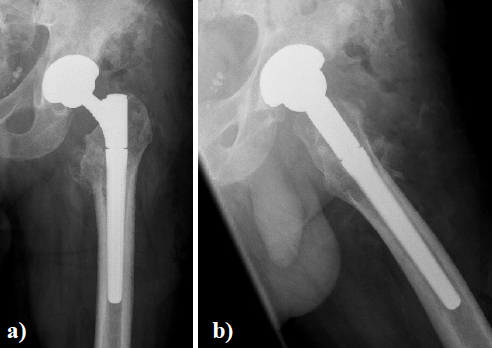

In August 2013 THA was performed due to a girdlestone situation after septic osteoarthritis of the hip (Figure 1) in a 46 year old male patient using a MRP Titan revision stem (Diameter: 18mm, length: 140 mm) (Peter Brehm GmbH, Weisendorf, Germany) and a cementless cup (Allofit - IT; Diameter 54 mm, Zimmer, Warsaw, USA) and a ceramic on ceramic bearing (head diameter: 36 mm) (Figure 2). The patient was 175 cm tall and weighed 105 kg (body mass index: 34.3 Kg/ m2). 2 weeks later revision surgery due to recurrent dislocation (Figure 3) was performed. Revision of the acetabular component was done using an Allofit - Classic- cup, Diameter 56 mm (Zimmer, Warsaw, USA)). The neck component was exchanged from small to medium size (Figure 4). A ceramic on PE bearing was implanted (head diameter: 32 mm). Postoperative healing was uneventful. The patient was out of any complaints. In February 2016 the patient started suffering from slight thigh pain but detected crepitation in the region of the left hip. X-ray of the left hip in 2 planes in May 2016 revealed an asymmetrically gap of the stem / neck junction (Figure 5). During revision surgery of the left hip breakage of the cone of the morse taper junction was visible (Figure 6). Removal of the well-fixed stem was performed via a distal fenestration. After fixation with cerclage wires a bended MRP Titan revision stem (Diameter: 19 mm, Length: 200mm with long neck and extension sleeve) was implanted using a 32 mm ceramic head (Figure 7). Postoperative healing was uneventful.

Figure 7. X - ray of the left hip in 2 planes: ap view a. and lateral; b. view shows revision arthroplasty of the hip using a long bended MRP Titan revision stem with long neck and extension sleeve.